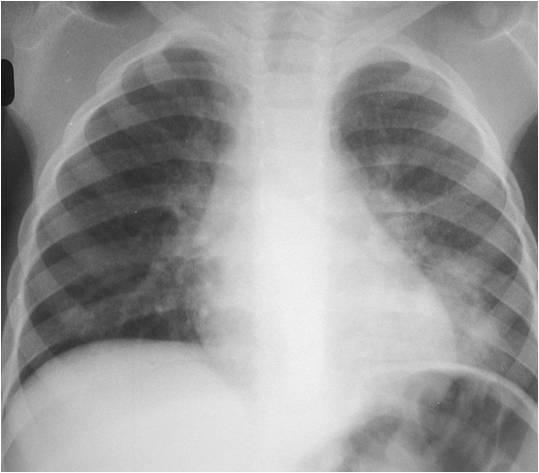

The following are examples of how Active TB may look on CXR:

Primary TB – LLL Infiltrate.

Mimics any pneumonia; occurs in debilitated pts, when Mtb first enters lung, and innate immune system unable to contain it.